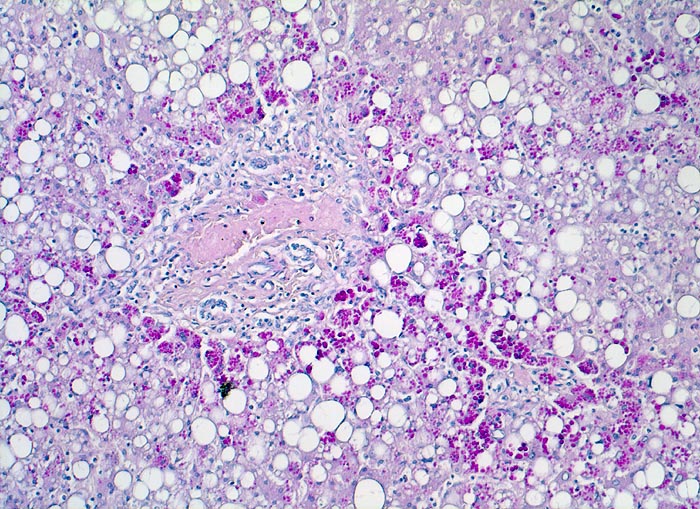

alpha-1-Antitrypsinmangel

Diastase-PAS positive Einschlüsse von alpha-1 Antitrypsin in periportalen Hepatozyten.

Bei Patienten mit alpha-1 Antitrypsinmangel wird das alpha-1 Antitrypsin nicht ins Blut abgegeben, sondern in Hepatozyten gespeichert, wo es zu einer Entzündung und Fibrose der Leber führt. Alpha-1 Antitrypsin schützt die Lunge vor Abbau durch Proteasen. Deshalb entwickeln Patienten mit alpha-1 Antitrypsinmangel ein Lungenemphysem.

Histologie

100